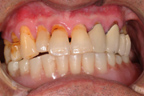

口腔內下顎兩側犬齒之植體。

下顎義齒底面之帽套。

上、下顎義齒密切咬合。